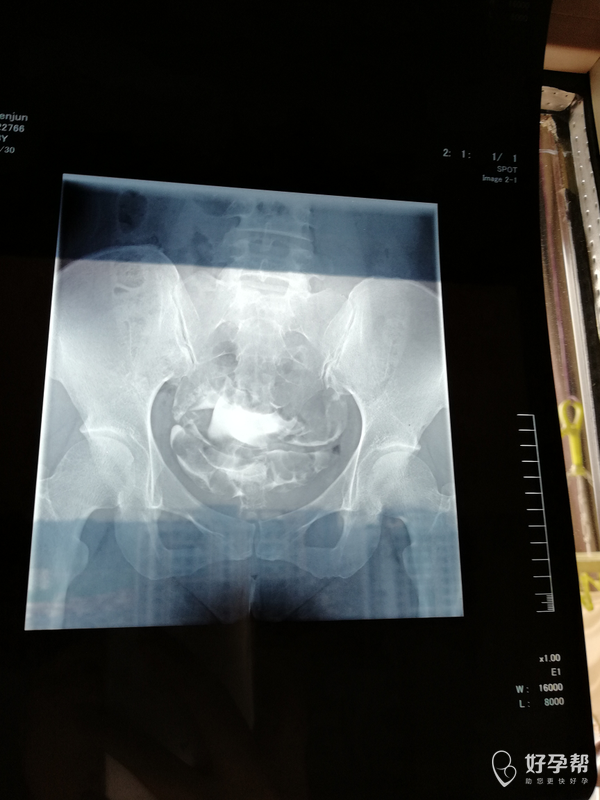

输卵管造影,双侧走行迂曲、僵硬,右侧末端弥散欠佳。